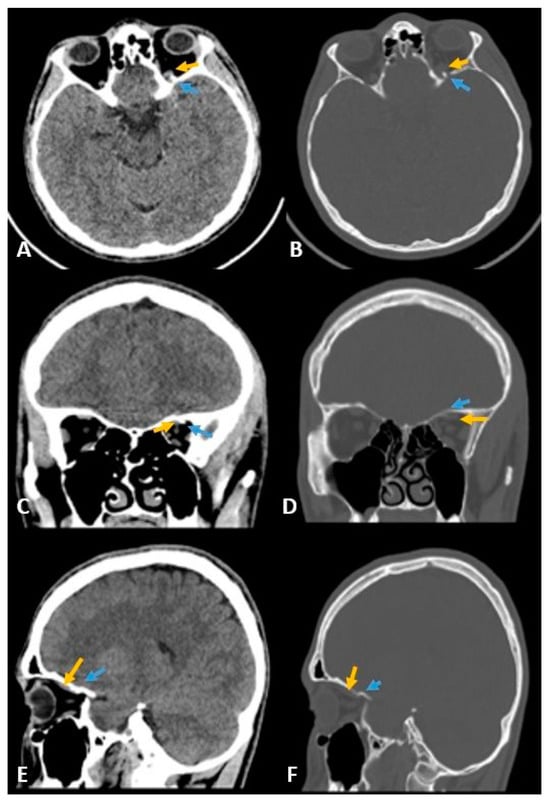

- Betts, A.M.; O’brien, W.T.; Davies, B.W.; Youssef, O.H. A systematic approach to CT evaluation of orbital trauma. Emerg. Radiol. 2014, 21, 511–531. [Google Scholar] [CrossRef] [PubMed]

- Lee, H.-J.; Jilani, M.; Frohman, L.; Baker, S. CT of orbital trauma. Emerg. Radiol. 2004, 10, 168–1672. [Google Scholar] [CrossRef] [PubMed]